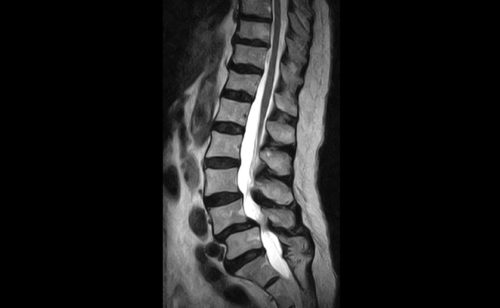

頸椎と頸椎の間にある椎間板と言われる衝撃吸収材に無理がかかり続けるようになり「頸椎椎間板ヘルニア」と言われる症状に進んだり、

筋肉も椎間板も衝撃吸収を拒否しだすと、ついには頸椎内部にある脊柱管を支える最後の砦である靭帯が衝撃吸収の役割を担うようになり、それが持続された場合、ついには靭帯が分厚くなることで、脊柱管内部が狭くなる「脊柱管狭窄症」という症状に至ることもあり得ます。